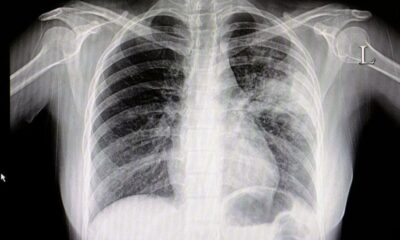

ABD’de yayımlanan yeni bir araştırmada; hamile olan, doğum kontrol hapı kullanan ya da hormon desteği alan kadınların koronavirüse (Covid-19) yakalanması durumunda kan pıhtılaşma riskinin ölümcül seviyede yüksek olabileceği belirtildi.

Araştırmanın eş yazarı Dr. Daniel Spratt koronavirüsün sağlık problemi yaşamayan insanlarda dahi kan pıhtılaşmasına neden olabileceğini belirtti.